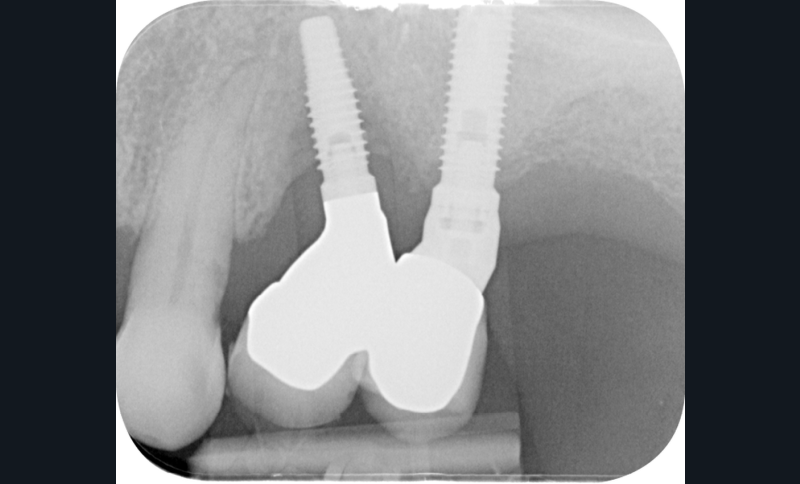

Type de connectique et pilier

Implant à connexion interne/externe

Au niveau d’un implant atteint de péri-implantite, la densité la plus importante de bactéries se trouve au niveau de la jonction pilier-implant [5]. La colonisation bactérienne de cette connectique se fait lors des manipulations…